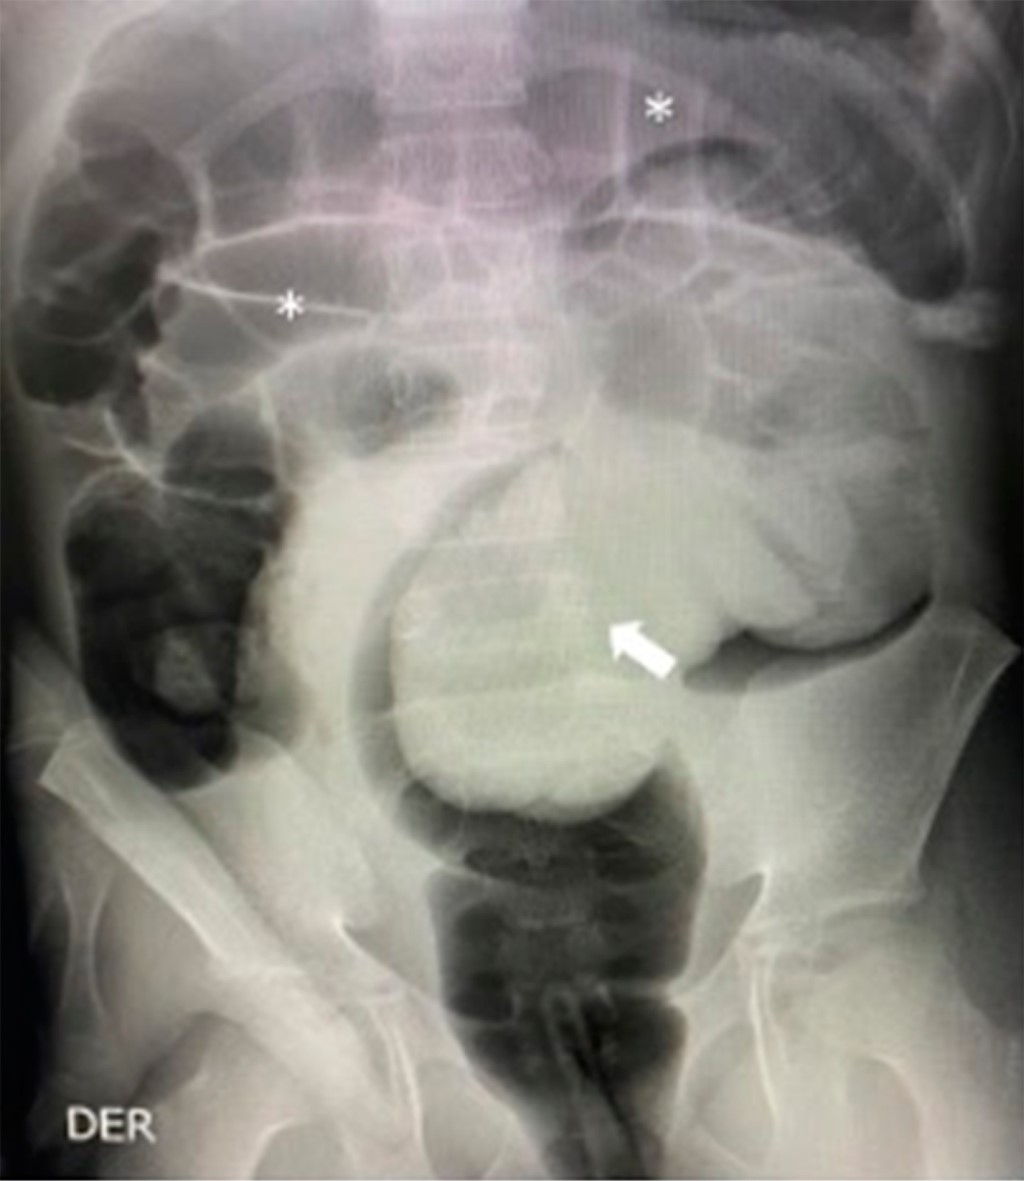

En la radiografía simple de abdomen se observó imagen de masa ocupando la luz del recto sigmoides, asociado a dilatación de colon transverso y asas de intestino delgado de manera proximal (Figura 1). Estos hallazgos se confirman en ultrasonografía abdominal, en el cual se reporta "signo de diana", sugestivo de invaginación intestinal en abdomen izquierdo.

Figura 1